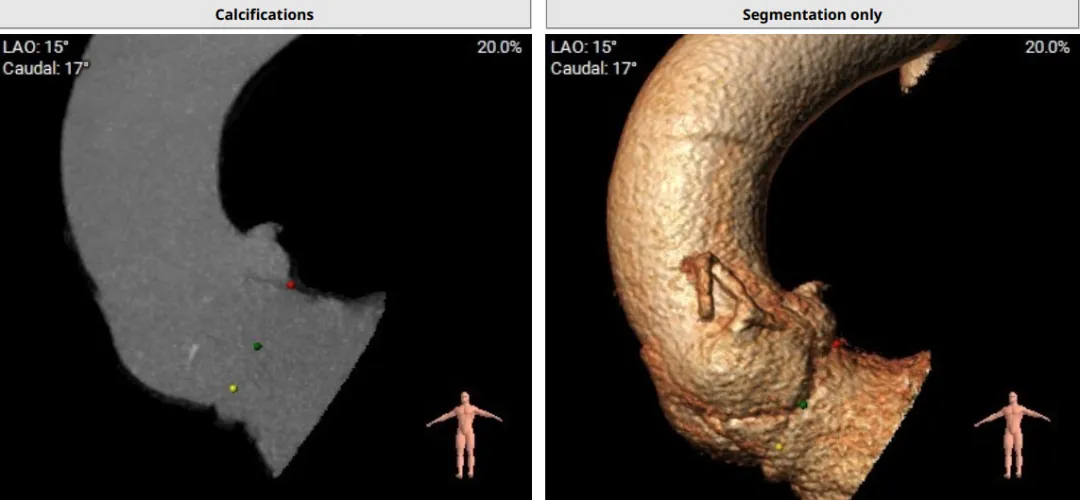

该患者术前CT评估提示:主动脉瓣Type-I型,瓣叶稍增厚,左右冠窦瓣叶交界粘连,无冠窦瓣叶轻微钙化,存在三个瓣窦,分布不均匀,左右冠窦融合;主动脉瓣环周长折算直径32.6mm;左心室流出道周长折算直径32.0mm,无钙化,无狭窄;STJ直径36.2mm,升主动脉直径38.6mm;左侧冠脉10.4mm ,瓣叶长10.8mm;右侧冠脉18.7mm,瓣叶长11.2mm;双侧冠脉开口高度可,无钙化;心尖-主动脉夹角偏大,左室主动脉夹角为120°;